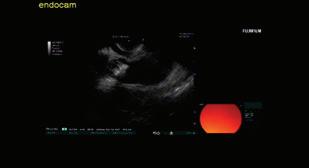

Доц. д-р Цветелина Тотомирова

60 РАДИОФРЕКВЕНТНА АБЛАЦИЯ НА ПАНКРЕАСНИ ТУМОРИ ПОД ЕНДОСОНОГРАФСКИ КОНТРОЛ Й. Петкова, П. Карагьозов, И. Тишков УРОЛОГИЯ